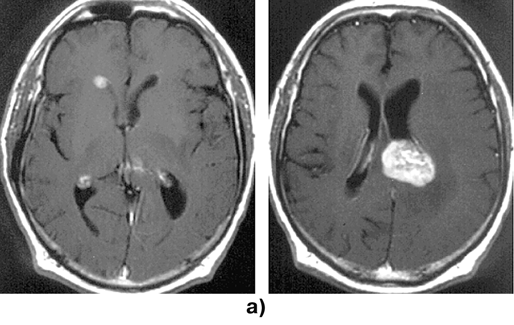

На МРТ или КТ (рис. 1) первичные лимфомы головного мозга в основном выглядят как объемные сóлидные образования гомогенно повышенной плотности, реже выявляются гипо— или изоденсные очаги. Больше 90% лимфом накапливают контраст, при этом гомогенное накопление контраста наиболее типично. Реже контрастное усиление происходит по периферии новообразования в виде кольца или не происходит вообще. В 10–30% случаев выявляется множественное поражение. Опухоли чаще располагаются супратенториально (лобные доли, подкорковые узлы, мозолистое тело, перивентрикулярно); субтенториальное распространение отмечается приблизительно в 25%, в основном в мозжечке; ствол мозга и спинной мозг поражаются редко. Первичные лимфомы ЦНС обычно локализуются в паренхиме мозга в отличие от системных лимфом («вторичное» поражение), при которых имеется лептоменингиальное распространение.

Рисунок 1. Первичные лимфомы ЦНС:

а — множественная первичная лимфома головного мозга (МРТ, Т1-взвешенные изображения с контрастным усилением, аксиальная проекция); б — лимфома медиальных отделов лобных долей, с обеих сторон распространяющаяся на колено мозолистого тела (до и через 1 год после стереотаксической биопсии и комбинированного лечения) (КТ с контрастным усилением, аксиальная проекция)